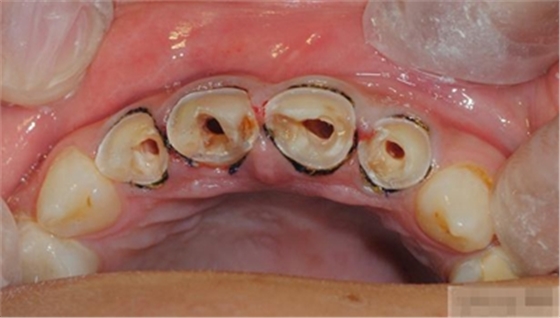

【主訴】上前牙充填物脫落兩個(gè)月

【病史】上前牙一年前行根管治療,充填物部分脫落,自覺影響美觀,從不敢笑,要求先行樹脂修復(fù)。(年齡:14歲)

【檢查】12,11,21,22,均行玻璃離子充填,各牙不同程度部分充填物脫落,探(—),叩(—),冷刺激無反應(yīng),無松動(dòng),牙齦顏色粉紅,質(zhì)地堅(jiān)實(shí)而有彈性,點(diǎn)彩正常,牙結(jié)石(—);牙髓活力測試無反應(yīng)。

【診斷】12,11,21,22牙體缺損